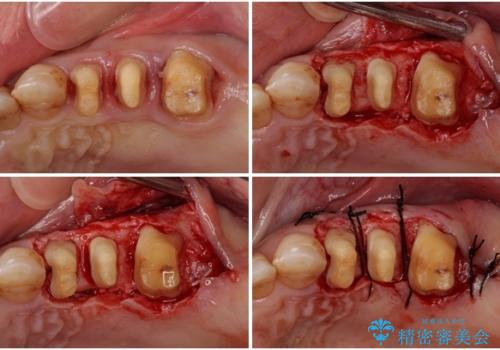

矯正治療を希望して来院されましたが、歯周病を併発していたため、矯正治療開始前の処置が非常に多くなりました。特に歯槽骨の再生治療を行ったため、外科処置後の静置期間が長くなり、4年弱の治療期間となりました。

治療後には咬みやすさだけでなく、前歯が大変審美的に仕上がり、患者様には大変満足していただきました。